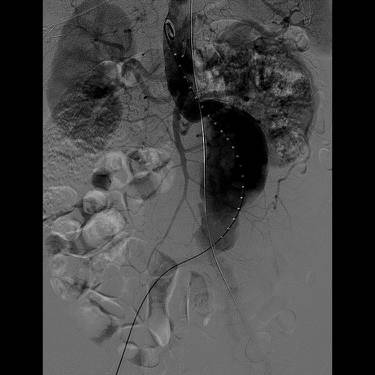

4.血管造影

主要作为腹主动脉瘤腔内修复术中的评估手段。对于肾功能不全的患者,可以考虑行MRA检查。